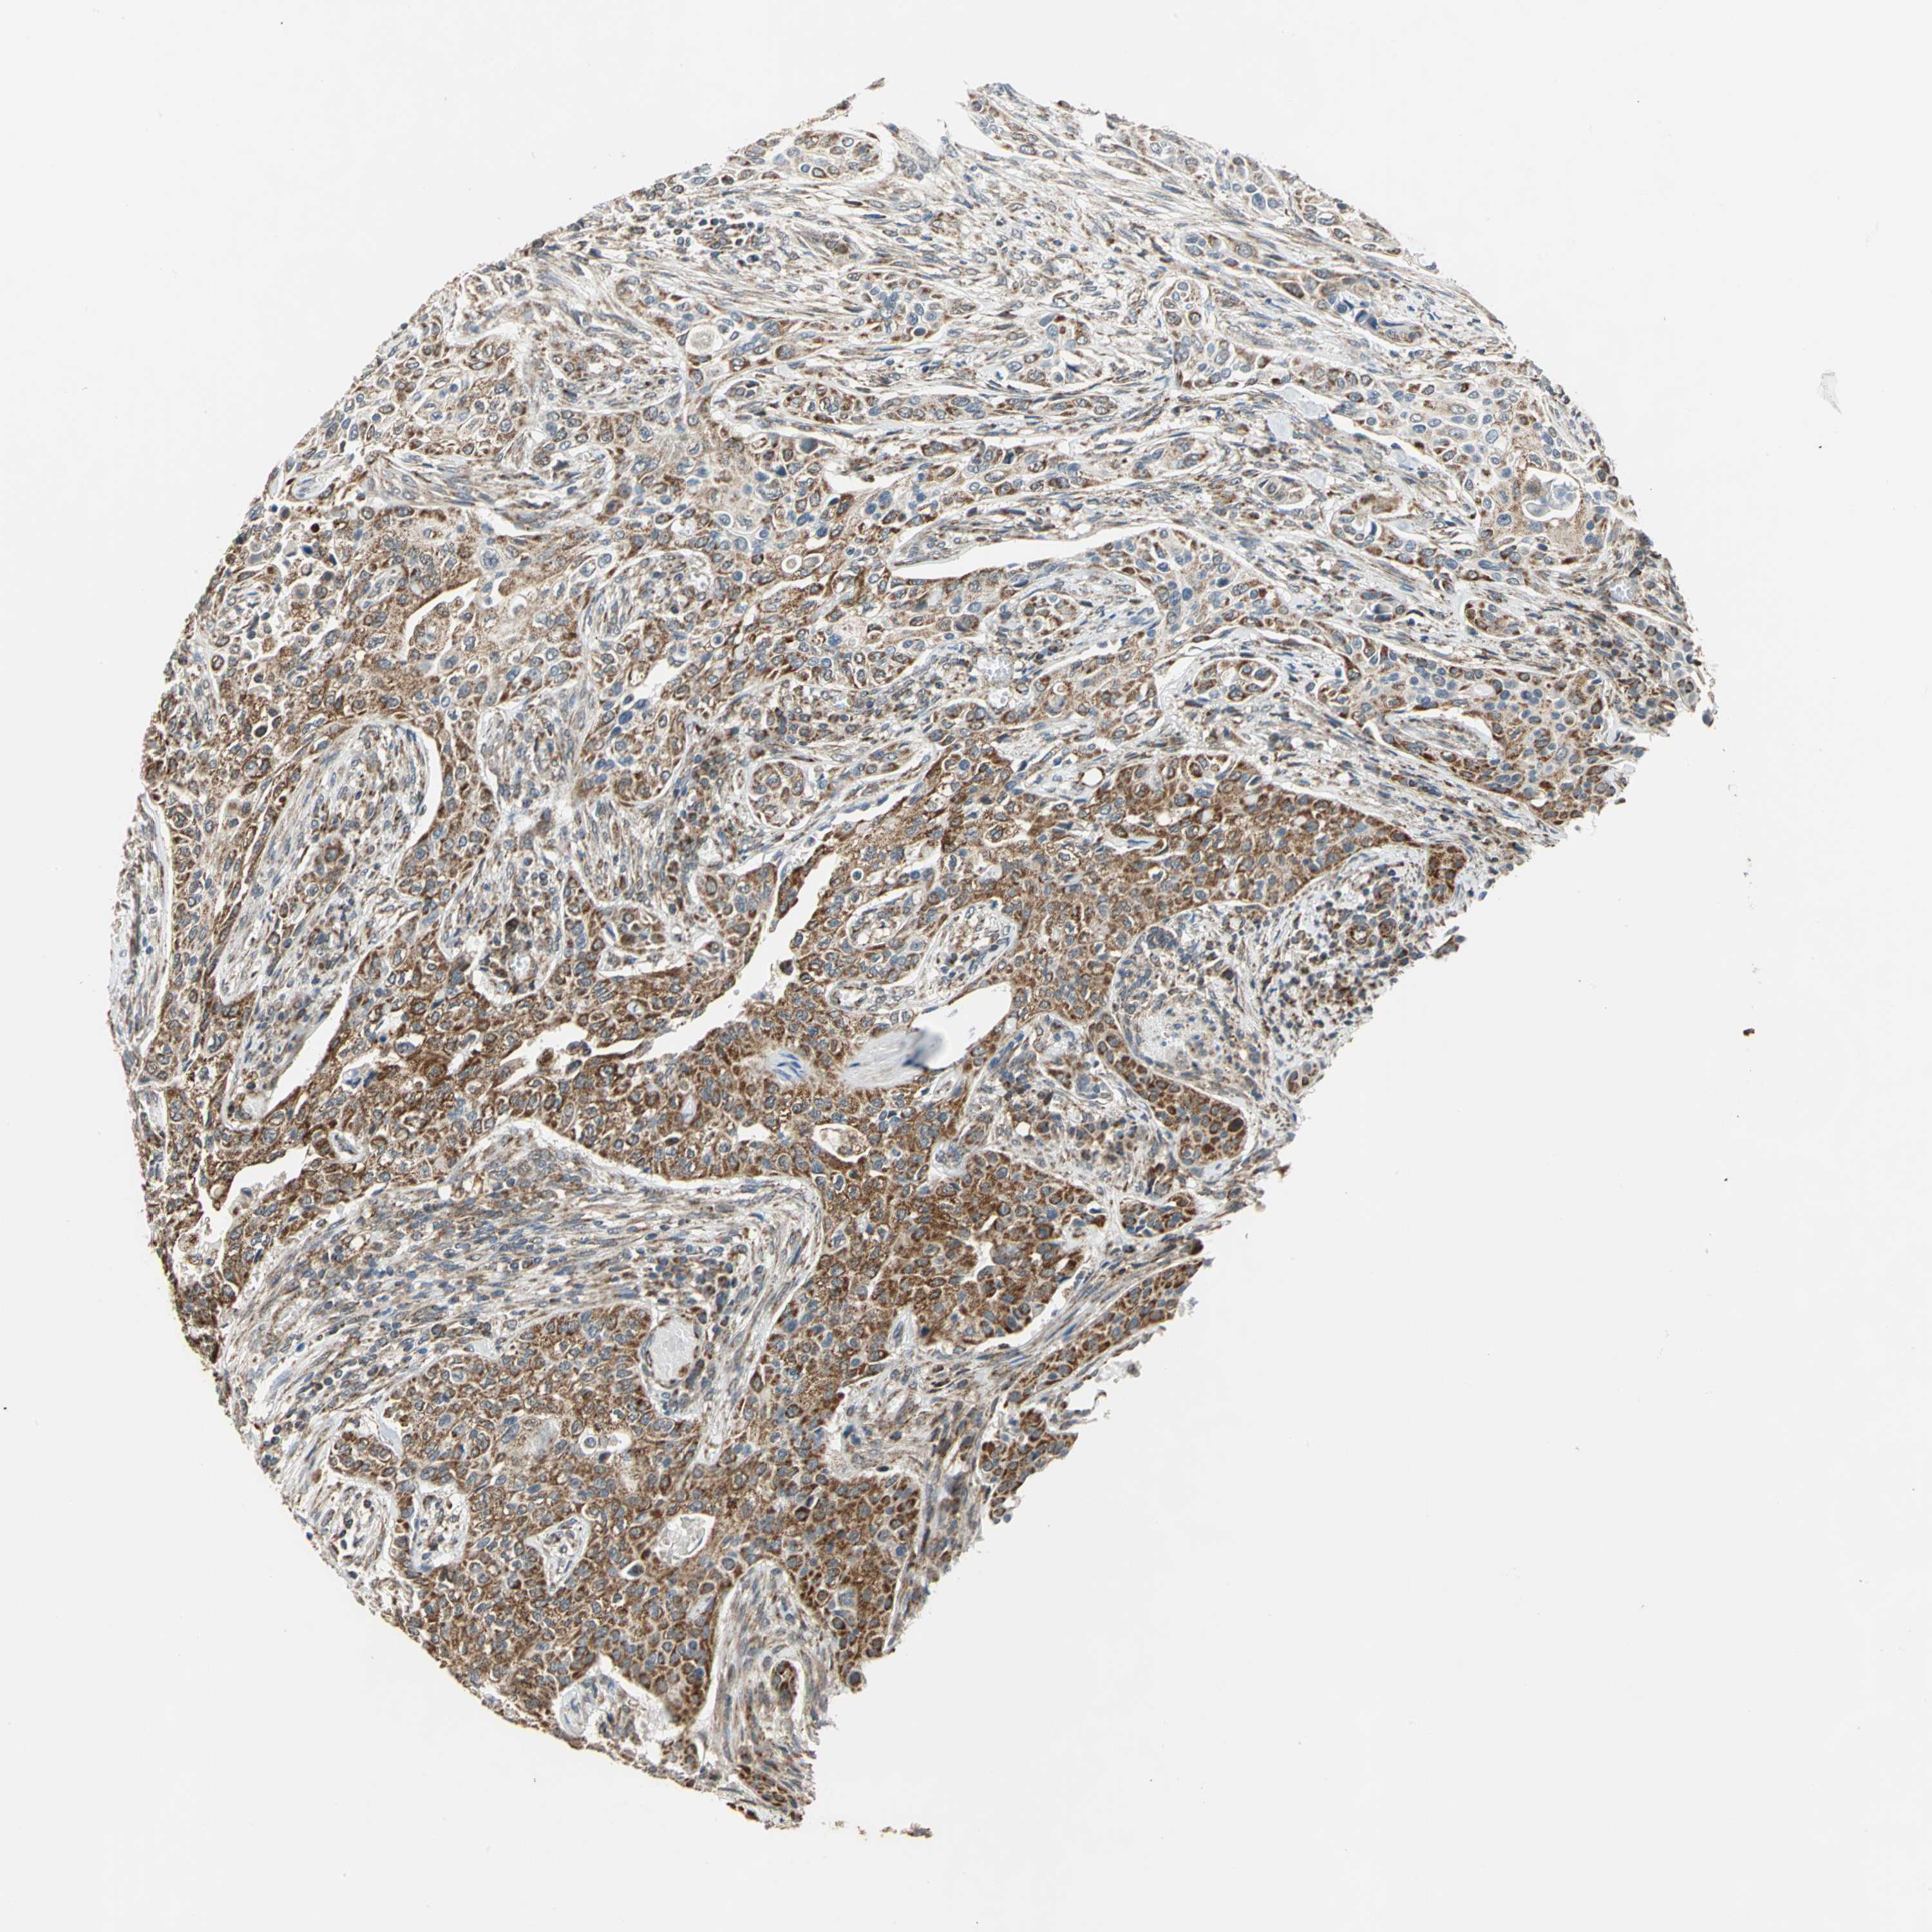

UROTHELIAL CANCER - Protein expressioni

A mouse-over function shows sample information and annotation data. Click on an image to view it in a full screen mode. Samples can be filtered based on level of antibody staining by selecting one or several of the following categories: high, medium, low and not detected. The assay and annotation is described here.

Note that samples used for immunohistochemistry by the Human Protein Atlas do not correspond to samples in the TCGA dataset.

Antibody stainingi

Antibody staining in the annotated cell types in the current human tissue is reported as not detected, low, medium, or high, based on conventional immunohistochemistry profiling in selected tissues. This score is based on the combination of the staining intensity and fraction of stained cells.

Each image is clickable and will lead to virtual microscopy that enables deeper exploration of all samples and also displays staining intensity scores, fraction scores and subcellular localization as well as patient and tissue information for each sample.

Antibody HPA006083

Antibody HPA007830

Urothelial carcinoma, High grade

Urothelial carcinoma, Low grade